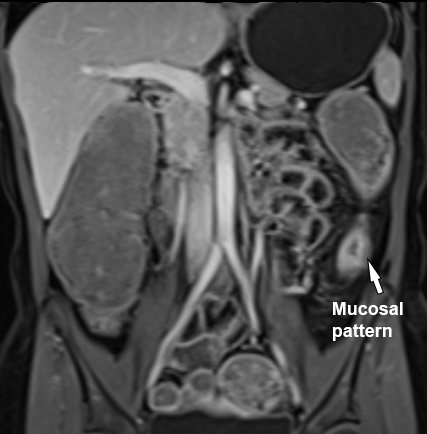

Kiểu ngấm thuốc

Kiểu ngấm thuốc của thành ruột có thể được phân loại theo một trong các dạng sau:

- Đồng nhất

- Niêm mạc

- Phân lớp

Hai kiểu ngấm thuốc sau chỉ có thể nhận biết khi thành ruột đã dày lên.

Hiện còn một số tranh luận về giá trị của kiểu ngấm thuốc.

Kiểu phân lớp được cho là phản ánh mức độ hoạt động bệnh nặng hơn so với kiểu niêm mạc, và kiểu niêm mạc lại nặng hơn kiểu đồng nhất (4).

Ngấm thuốc niêm mạc

Biểu hiện là thành ruột dày với lớp niêm mạc ngấm thuốc tăng so với các lớp bên ngoài.

Hình ảnh là ảnh T1 sau tiêm thuốc tương phản từ với kiểu ngấm thuốc niêm mạc tại hồi tràng cuối (mũi tên).

Lớp giữa và lớp ngoài ngấm thuốc tương đối ít.

Bệnh nhân nữ 48 tuổi, đang điều trị bằng thuốc kháng TNF, được chỉ định nội soi đại tràng.

Phát hiện hẹp lòng ruột ở đại tràng sigma, không thể vượt qua được khi nội soi.

MR-enterography được thực hiện để đánh giá mức độ lan rộng của chỗ hẹp.

Ruột non bình thường, nhưng ghi nhận các đoạn hẹp ở đại tràng xuống và đại tràng ngang.

Cả hai đoạn hẹp đều có thành ruột dày đến 8 mm và ngấm thuốc rõ rệt theo kiểu niêm mạc ở đại tràng xuống và kiểu phân lớp ở đại tràng ngang.

Giãn ruột trước chỗ hẹp được ghi nhận ở cả hai đoạn.

Do các chỗ hẹp này không hiện diện khi nội soi đại tràng trước khi điều trị kháng TNF, nhiều khả năng chúng đã hình thành trong quá trình điều trị.

Do đó, quyết định phẫu thuật cắt đại tràng gần toàn bộ với miệng nối hồi-sigma đã được đưa ra.